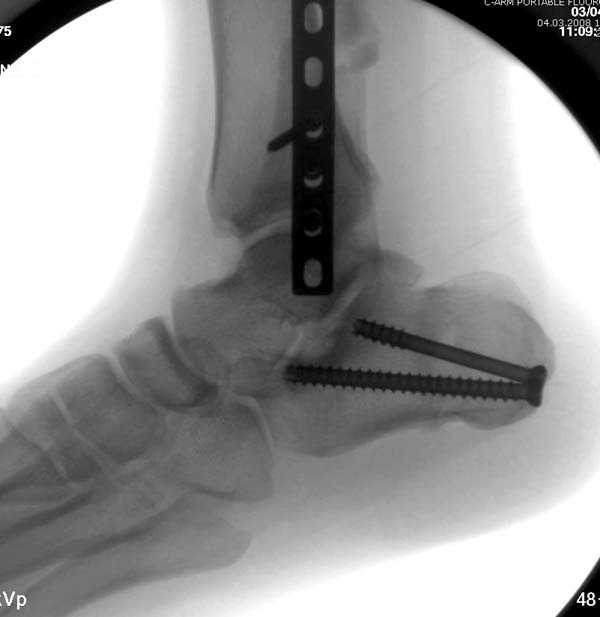

Проведена обычная стандартная процедура по исправлению неудовлетворительного состояния голеностопного сустава, где кроме удлинения малоберцовой с применением compression tension device за проксимальный конец пластины, проведено замещение трикортикальным графтом из крыла, освобождение синдесмоза и медиальной щели от

фибротических масс с фиксацией.